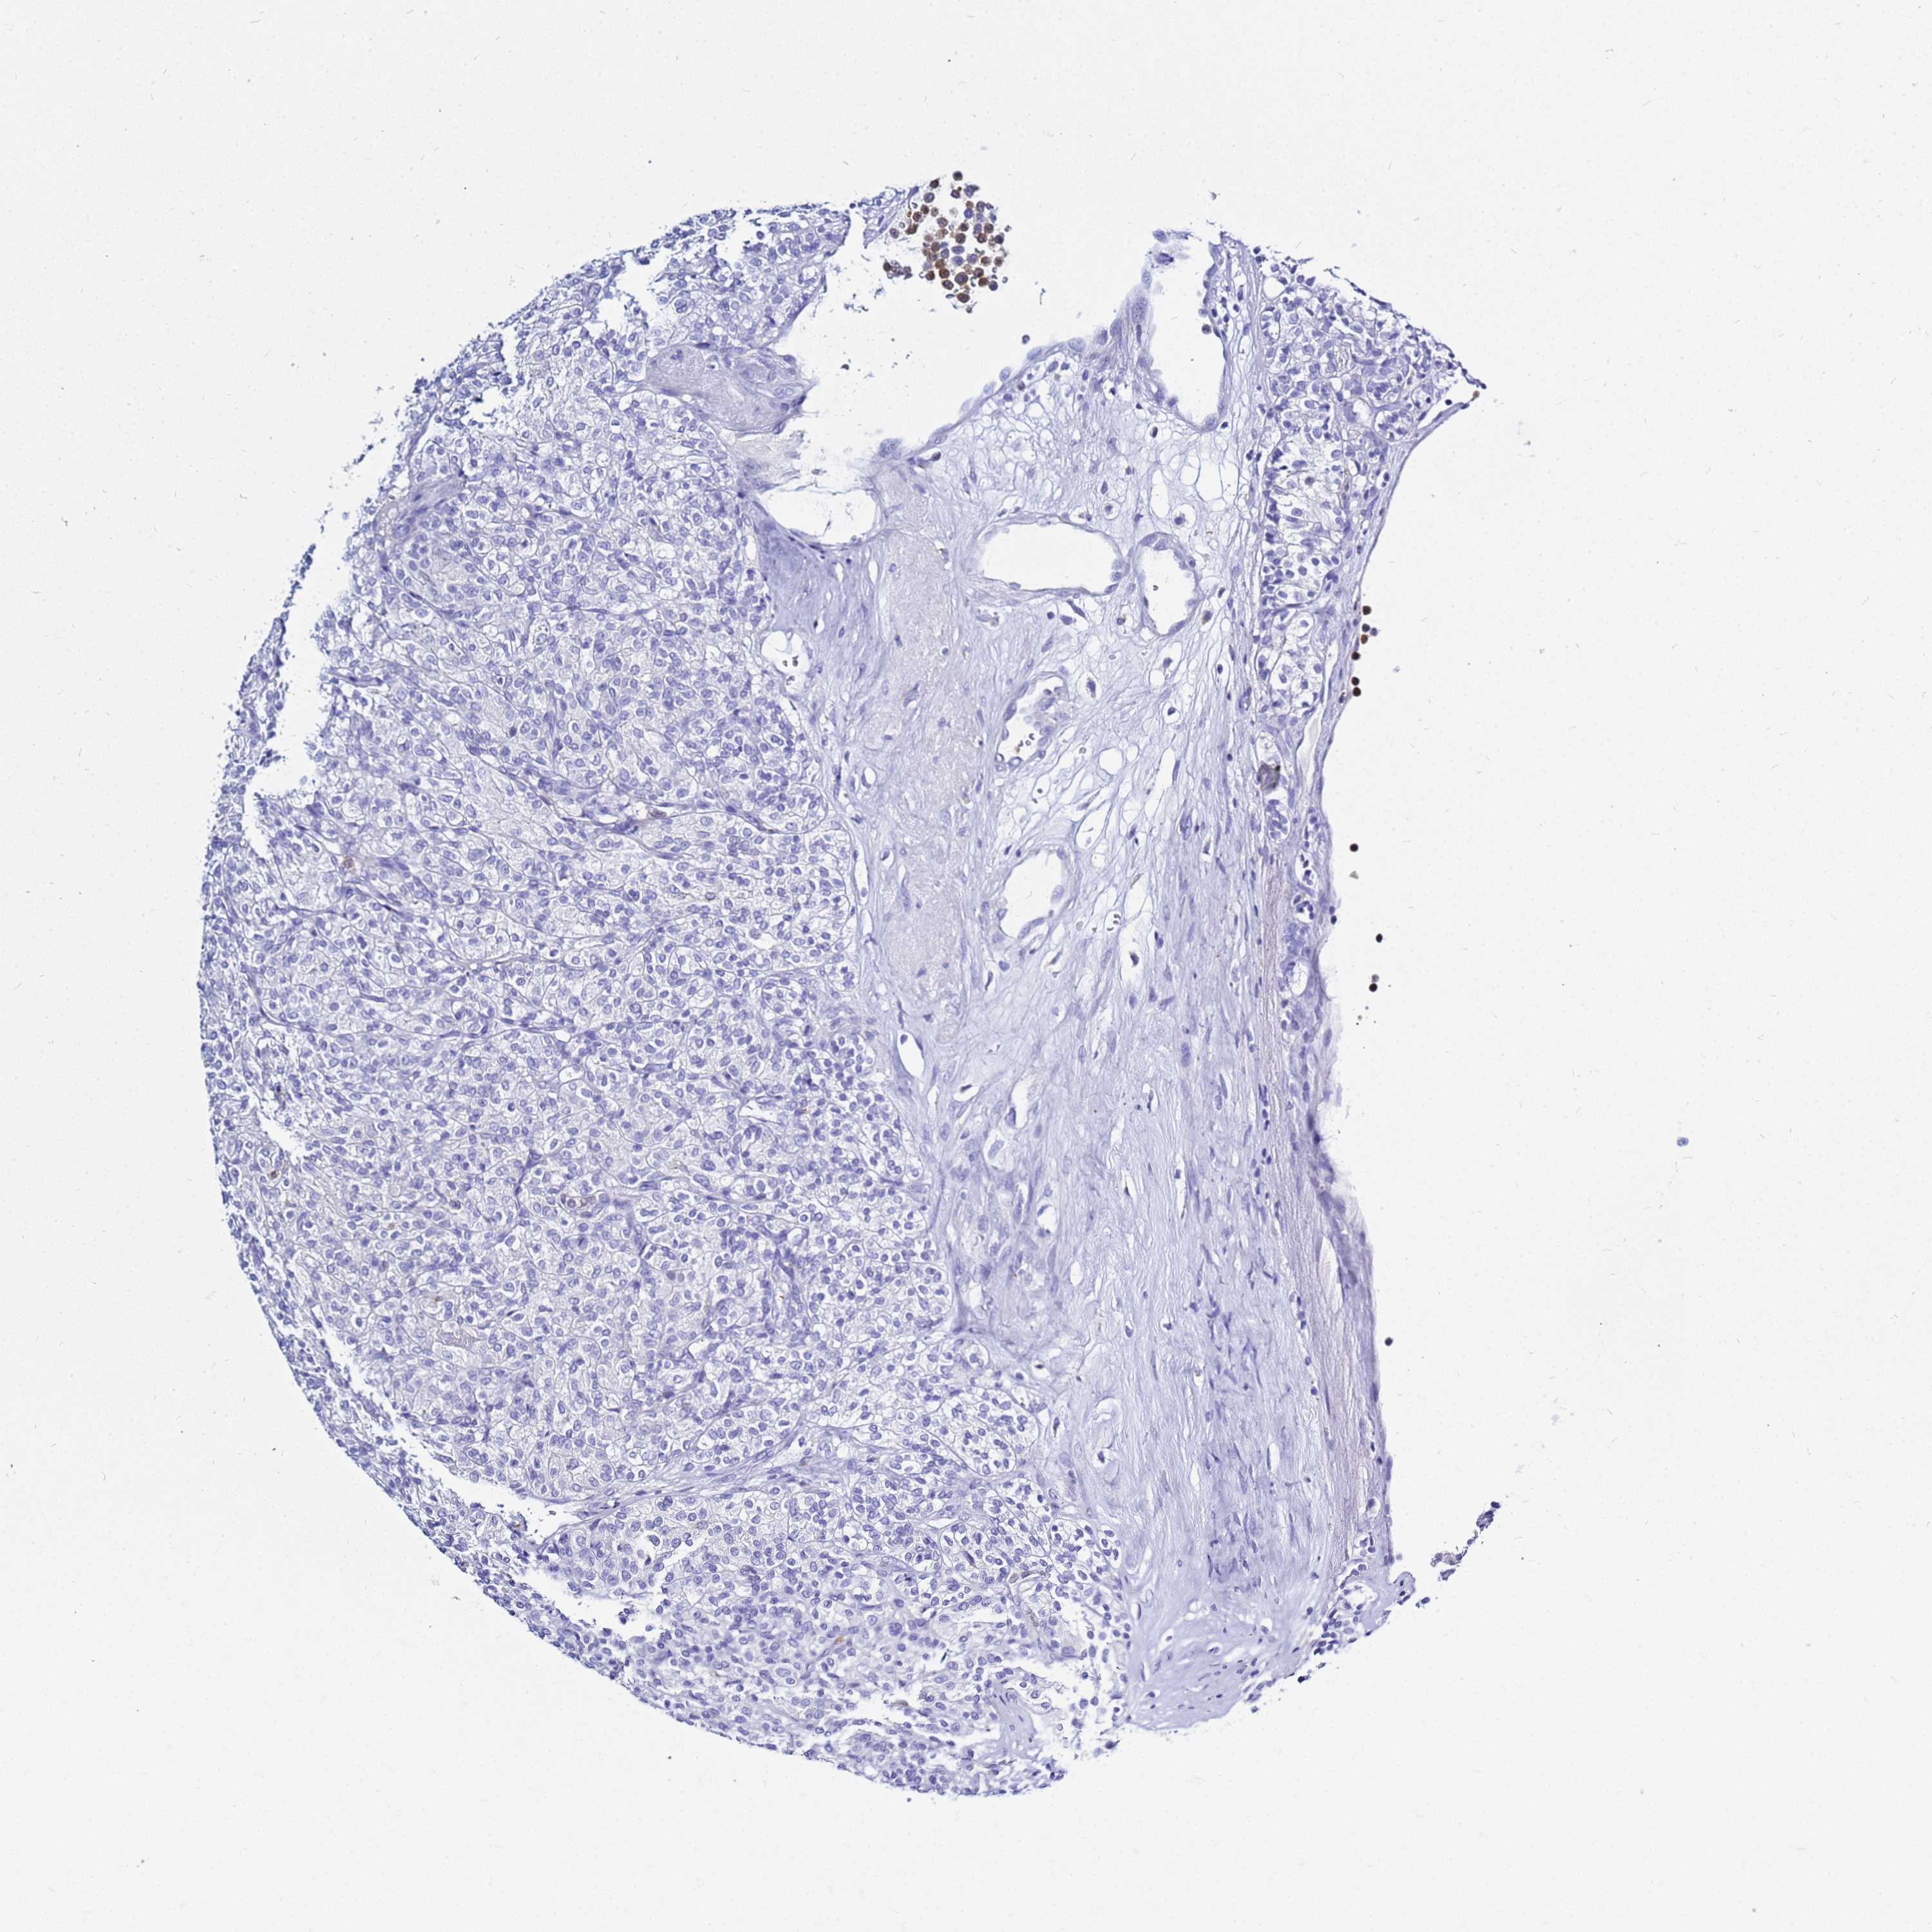

KIDNEY RENAL CLEAR CELL CARCINOMA (TCGA) - Interactive survival scatter ploti

The Survival Scatter plot shows the clinical status (i.e. dead or alive) for all individuals in the patient cohort, based on the same data that underlies the corresponding Kaplan-Meier plots. Patients that are alive at last time for follow-up are shown in blue and patients who have died during the study are shown in red.

The x-axis shows the expression levels (FPKM) of the investigated gene in the tumor tissue at the time of diagnosis. The y-axis shows the follow-up time after diagnosis (years). Both axes are complimented with kernel density curves demonstrating the data density over the axes. The top density plot shows the expression levels (FPKM) distribution among dead (red) and alive patients (blue). The right density plot shows the data density of the survived years of dead patients with high and low expression levels respectively, stratified using the cutoff indicated by the vertical dashed line through the Survival Scatter plot. This cutoff is automatically defined based on the FPKM cutoff that minimizes the p-score. The cutoff can be changed by dragging the vertical line or by entering a cutoff value in the square labeled "Current cut-off".

Under the Survival Scatter plot the p-score landscape (black curve; left axis) is shown together with dead median separation (red curve; right axis). Dead median separation is the difference in median mRNA expression between patients who have died with high and low expression, respectively. It is calculated as follows: median FPKM expression of dead patients with high expression - median FPKM expression of dead patients with low expression. This is intended to aid the user in visually exploring custom cutoffs and the associated p-scores and dead median separation.

Individual patient data is displayed and can be filtered by clicking on one or more of the category buttons on the top of the page. Categories describing expression level and patient information include: high, low, alive, dead, female, male and tumor stages. The scale of the x-axis can be toggled between linear and log-scale by clicking on the "x log" button. Mouse-over function shows TCGA ID, patient information and mRNA expression (FPKM) for each patient.

& Survival analysisi

Kaplan-Meier plots summarize results from analysis of correlation between mRNA expression level and patient survival. Patients were divided based on level of expression into one of the two groups "low" (under cut off) or "high" (over cut off). X-axis shows time for survival (years) and y-axis shows the probability of survival, where 1.0 corresponds to 100 percent.

CSTA is not prognostic in Kidney Renal Clear Cell Carcinoma (TCGA)

Best expression cut offi

Based on the FPKM value of each gene, patients were classified into two groups and association between prognosis (survival) and gene expression (FPKM) was examined. The best expression cut-off refers the FPKM value that yields maximal difference with regard to survival between the two groups at the lowest log-rank P-value. Best expression cut-off was selected based on survival analysis .

When clicking on this number, the vertical dashed line indicating cut-off, the interactive survival plot, and the Kaplan-Meier curve will be adjusted to show results based on the best expression cut-off.

: 12.41

P scorei

Log-rank P value for Kaplan-Meier plot showing results from analysis of correlation between mRNA expression level and patient survival.

N/A

TCGA RNA samplesi

RNA-seq data is reported as average FPKM (number Fragments Per Kilobase of exon per Million reads), generated by the The Cancer Genome Atlas (TCGA) .

Normal distribution across the dataset is visualized with box plots, shown as median and 25th and 75th percentiles. Points are displayed as outliers if they are above or below 1.5 times the interquartile range. FPKM values of the individual samples are presented next to the box plot.

Average pTPM 9.0

Number of samples 521